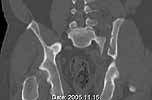

Was hemodynamic unstable at local ER, sent to our Trauma center where circumferential pelvic binder placed and pt. stabilized with fluid, blood, and rewarming. Angiography not performed. An extraperitoneal bladder disruption was found, uro elected to treat non-operatively. Initial xray (not shown) demonstrated 5-7 cm wide at symphysis and SI joint. The first image attached is of CT once binder is in place.